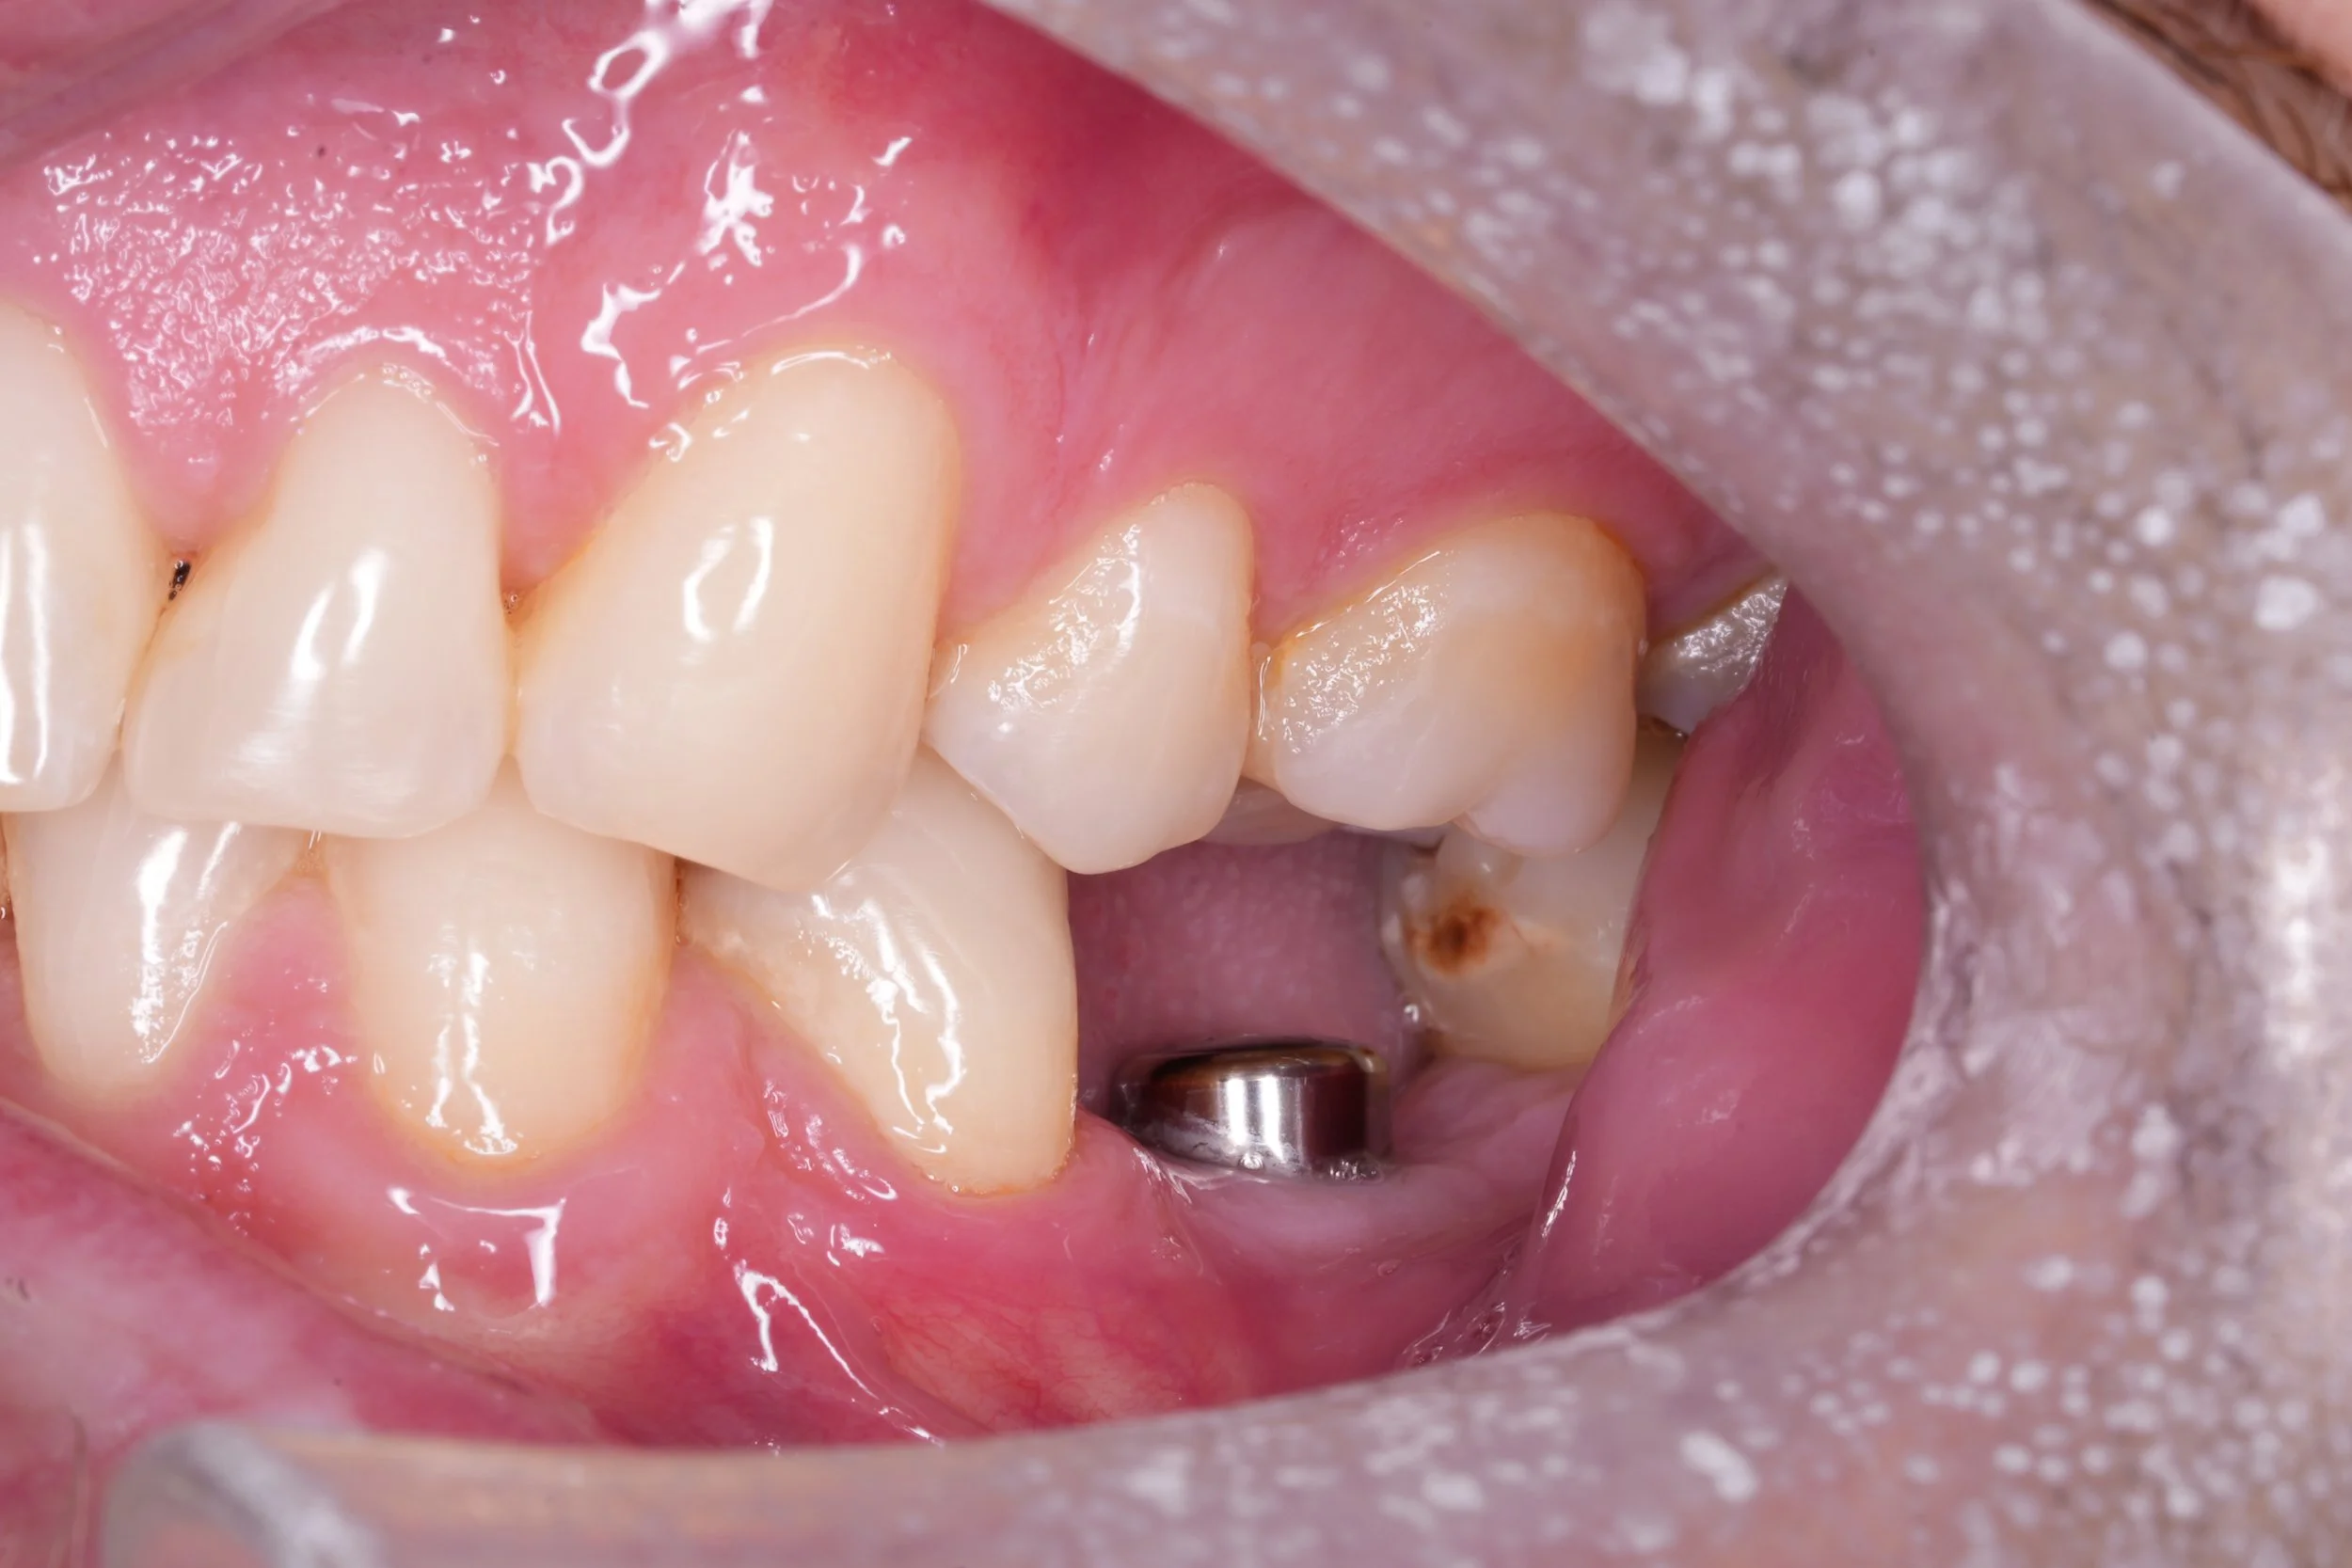

Dental Implants